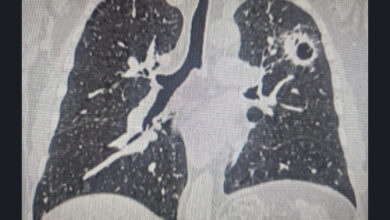

Рак легкого: ранняя диагностика, факторы риска и профилактика

Рак легкого остается одним из самых серьезных онкологических заболеваний, однако его ранняя диагностика рака легкого значительно повышает шансы на успешное лечение. Главный онколог из Новосибирска, заместитель главного врача Новосибирского онкодиспансера Вадим Козлов, подчеркивает критическую важность регулярной диспансеризации для выявления рака легкого. По его словам, около трети всех случаев заболевания…

Новосибирские онкологи удалили три опухоли у пациента: история успеха

В Новосибирске медики совершили настоящий прорыв в онкологии, успешно удалив сразу три опухоли у одного пациента. Эта сложная история лечения рака подчеркивает высокий профессионализм новосибирских онкологов и возможности современной медицины. Изначально мужчине был диагностирован центральный рак правого легкого. Специалисты приняли решение о частичном удалении легкого, при этом сохранив здоровые…